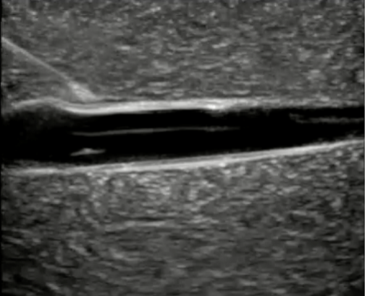

Ultrasound-guided peripheral intravenous (USGPIV) access has become an increasingly valuable tool in pediatric vascular access, especially in patients with DIVA, such as those with obesity, chronic illness, or poor peripheral vein visibility. The use of real-time ultrasound enhances visualization of deeper or poorly visible veins, allowing for higher success rates and fewer cannulation attempts compared to traditional landmark-based approaches. (See Figure 2.)

Figure 2. Long Axis Approach of a Catheter into a Vessel |

![]() |

Courtesy of Daniel Migliaccio, MD |